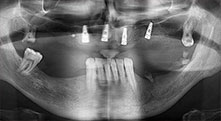

Could you describe briefly, for example, your procedure for mobilizing bone blocks for transplantation?

Bratu: We prefer to harvest bone from the external oblique ridge of the posterior mandible, not from the interforaminal region. After the soft-tissue incision, we use the new saws to define the amount of bone to harvest. With this approach, we also use them for the entire preparation in almost 80% of cases. We may also use other piezo instruments and then at the end a chisel to mobilize the block. We find that this is a very effective surgical technique.

Could you give us a few surgical tips and tricks from your hospital?

Bratu: We like to use the sandwich technique for augmentation in the lateral mandible. A bone cover is prepared with the piezo saw and the crestal fragment is fixed with microscrews. We place a mixture of autologous bone and xenogenic bone replacement material in between. This works very reliably. You should always ensure sufficiently dimensioned vertical cuts when splitting the alveolar ridge in the mandible. Otherwise the bone may fracture easily.